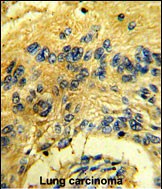

- Formalin-fixed and paraffin-embedded human lung carcinoma reacted with CDK3 Antibody (N-term Y19), which was peroxidase-conjugated to the secondary antibody, followed by DAB staining. This data demonstrates the use of this antibody for immunohistochemistry; clinical relevance has not been evaluated.